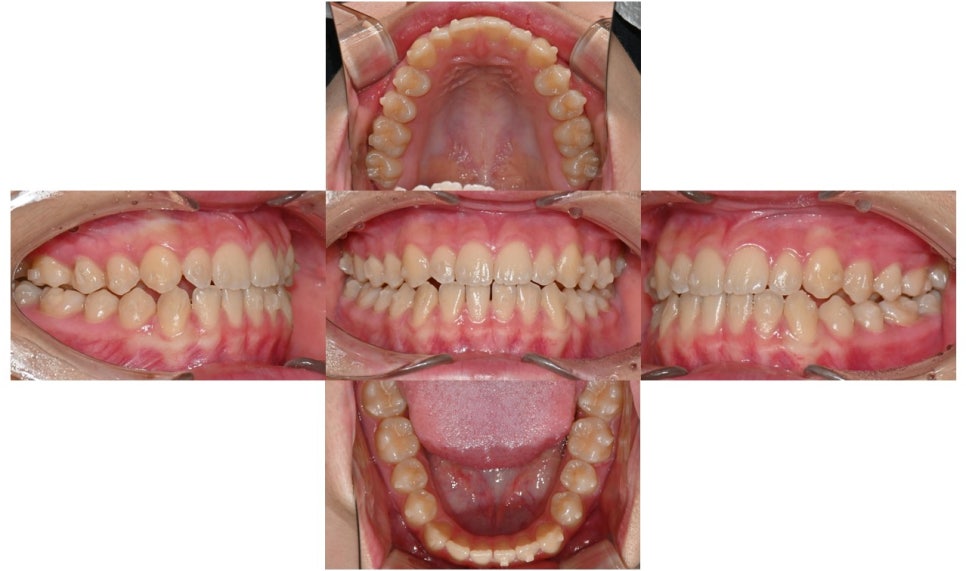

치료 시작 8개월 후 사진으로 치아 사이에 벌어졌던 공간은 거의 다 닫혔으며 어금니 교합도 개선되었습니다. 위아래 치아 중심선도 일치하고 있습니다. 현재 미세하게 치아 위치 조정하며 마무리 중입니다.

치료 시작 8개월 후

치료 전후 구내사진